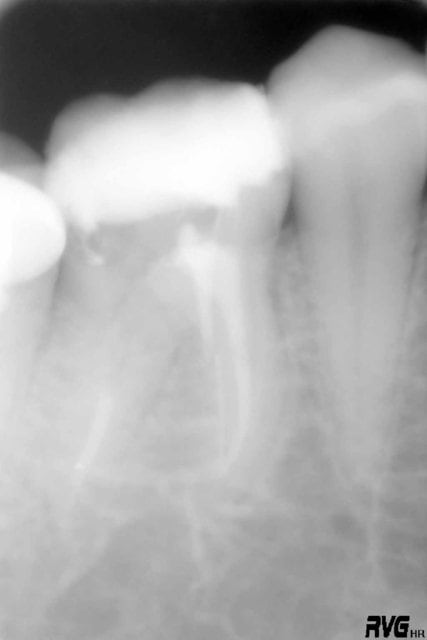

Je commence avec ce bout de F2 que j'ai ostéointégré :( à l'extrémité de la racine Distovestibulaire de cette 17. A l'origine, un "buggage" du localisateur d'apex. Je ferai dorénévement tout de meme une petite rvg de controle....